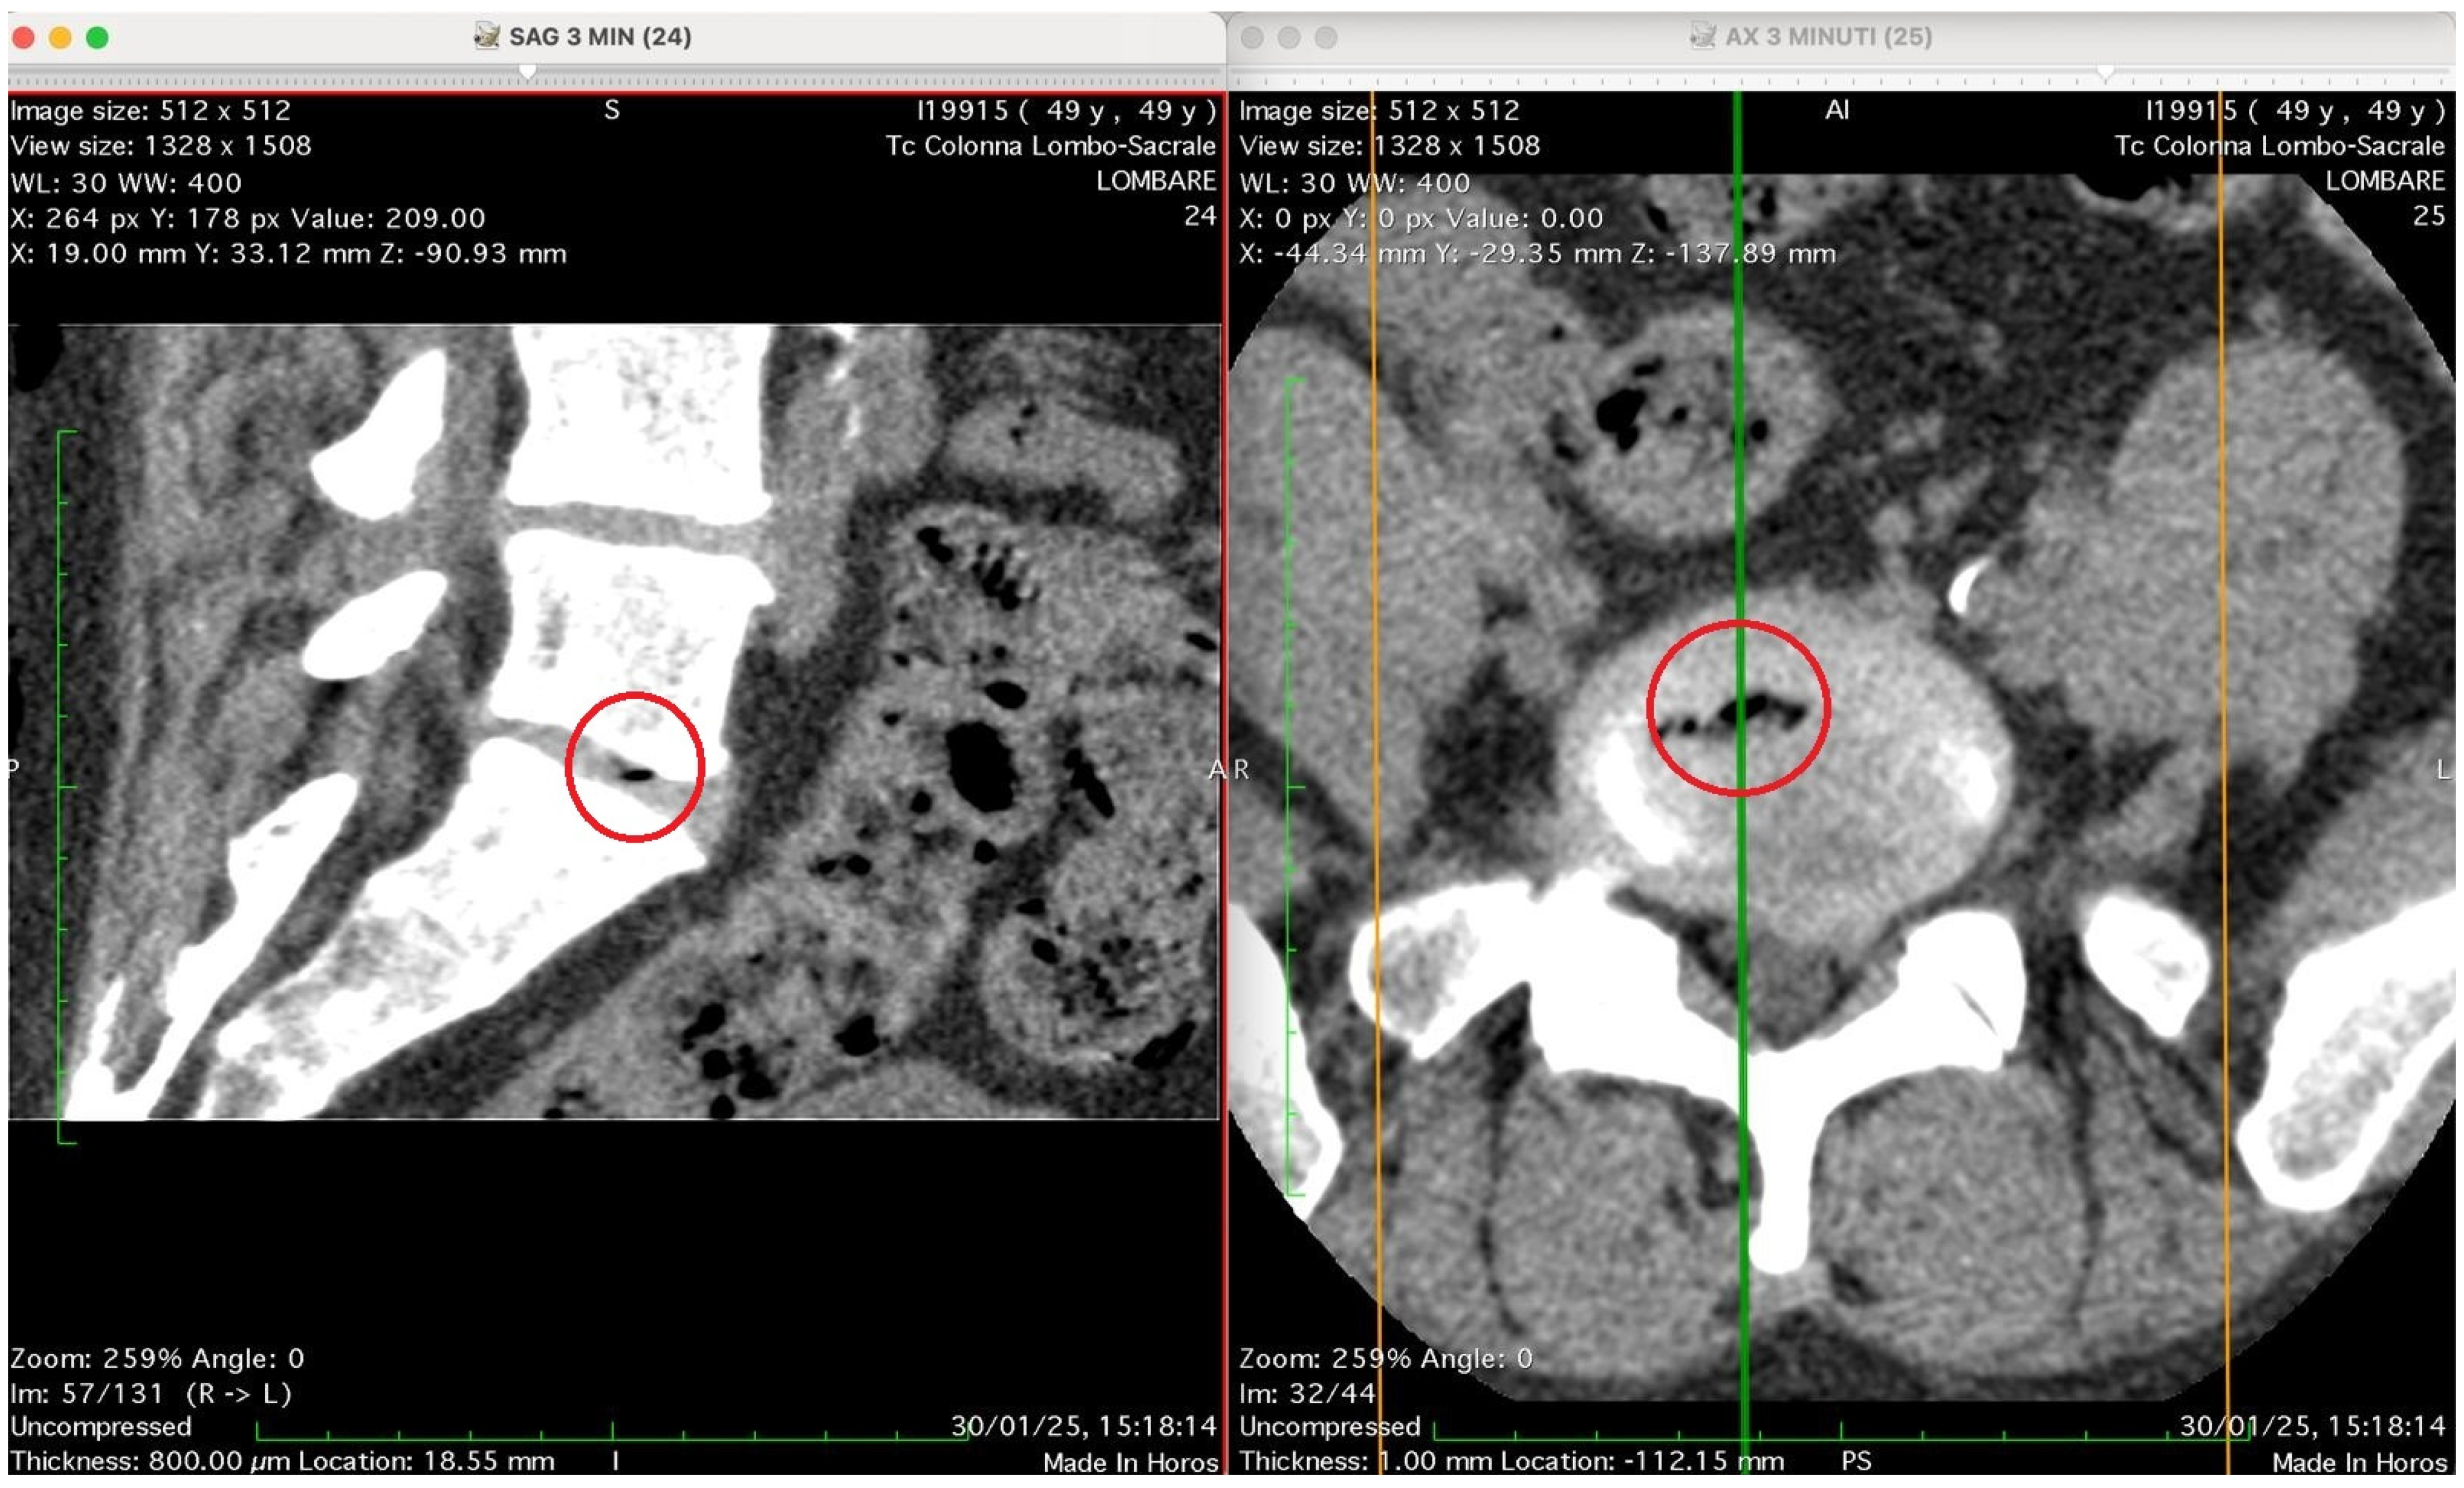

Figure 2, Figure 3, Figure 4 and Figure 5 show four computed tomography (CT) scans, along a time-course analysis, of the lumbosacral spine, visualized in sagittal (left) and axial (right) planes, from an exemplificative male patient (49 years) with L5-S1 herniated disc, undergoing an experimental setting of oxygen–ozone therapy via the intramuscular approach (Revolution™ CT, GE-Healthcare, Chicago, IL, USA). The very low-density ozone gas (hypodense, dark black within cred circles), spreads over the intervertebral disc within the time course of less than 10–20 min, assessing that ozone in the oxygen medium really reaches the morpho-functional area where the herniated disc is present in short times. A possible explanation is provided in the next paragraph.

Figure 3 shows two CT images of the lumbosacral spine (Tc Colonna Lombo-Sacrale), acquired in sagittal and axial planes and synchronized through cross-reference lines at time 3 min. The left panel (SAG 3 MIN, slice 24) is a sagittal reconstruction of the lumbar column. Within the intervertebral disc (most likely at the L4–L5 or L5–S1 level), a small, sharply demarcated hypodense focus (marked by the red circle) is visible. This area has the typical appearance of gas (air) within the nucleus pulposus, with no surrounding soft-tissue reaction or haemorrhagic density. It lies entirely within the discal space, not extending into the vertebral endplates. The right panel (AX 3 MIN, slice 25–26): shows the axial view at the corresponding level and confirms the presence of a gas bubble within the centre of the intervertebral disc, as shown by the red circle. The gas appears as a very low-attenuation (black) region surrounded by the denser annulus fibrosus and adjacent vertebral bone. The vertebral canal and neural foramina appear preserved; there is no evidence of epidural gas or acute paravertebral collection. Technical details: Image matrix: 512 × 512 WL/W: 30/400 (optimized for soft-tissue and bone visualization) Slice thickness: 0.8 mm Acquisition time: 30 January 25, 15:18:14 Interpretation summary: The CT pair demonstrates a localized intradiscal gas focus consistent with a vacuum phenomenon or gas migration following paravertebral oxygen–ozone injection. The localization (intradiscal, central, sharply defined) and absence of adjacent tissue emphysema suggest that gas has entered the disc space, likely through microfissures of the annulus fibrosus, rather than being introduced directly by an intradiscal needle placement.